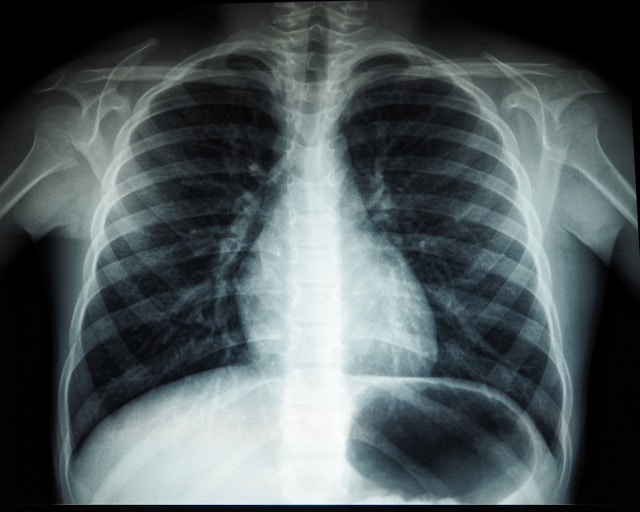

צילום שהראה את הגידול בעמוד השדרה לא פוענח נכון, והמטופל גילה על מחלתו באיחור של 9 חודשים. רשת המכונים: "זה כמו הציור השבועי לילד - קשה למצוא"

התובע (72), חשמלאי במקצועו, סבל בתחילת 2019 מדלקת ריאות. חרף טיפול אנטיביוטי שקיבל, הוא עדיין סבל מקוצר נשימה וכאבים המקרינים לכתפו השמאלית, ולכן הופנה לבדיקת CT במכון מאר, אשר נערכה בתחילת אפריל אותה שנה. בבדיקה נראו ממצאים המצביעים בבירור על גידול שפשט בעמוד השדרה של האיש, ו'אכל' מספר חוליות בגבו.

בתביעתו טען האיש שאי-גילוי הסרטן בזמן מהווה רשלנות של המכון. לשיטתו ה'נגיסה' בשלוש מחוליותיו, כפי שנצפתה בבדיקה מאפריל 2019, מלמדת על הימצאו הבירור של הגידול הסרטני, ומכאן שעל הרשת לפצותו בשל נזקיו.

אבל את השופטת גרדשטיין-פפקין טקטיקת ההגנה הייחודית של רשת המכונים לא שכנעה. היא כתבה שבניגוד למשחק הילדים הוותיק של ג'קי - בו מדובר באינסוף אפשרויות נסתרות - הרי שבפני הרדיולוג פרוש צילום של חלק גופני אותו הוא מכיר היטב, כאשר תפקידו מתמצה באיתור חריגה מהמבנה האנטומי המוכר לו, על רקע ההפניה מהרופא והתסמינים מהם סבל המטופל.

בהקשר לכך הדגישה השופטת כי בדיקת ה-CT שעבר התובע באפריל 2019 הדגימה בבירור גידול סרטני, שגם אדם שאינו מתמחה ברפואה מסוגל להבחין בו. יתרה מכך, מומחית הנתבעת בעצמה הודתה במהלך חקירתה כי במקרה זה - בו נצפה הרס בעצם, ולא רק נזק לרקמת הריאה - היה צריך לכל הפחות להתריע על ממצא סרטני אפשרי.

"אמרו אם כן, נזק כזה של הרס חוליות, שניתן לראותו גם על-ידי הדיוט, אינו נלמד רק בבחינה בדיעבד, אלא מהווה חריגה ברורה מפרקטיקה מקובלת", כתבה השופטת וסיכמה: "נוכח האמור, במקרה בולט בו היה מקום לאתר את הממצא נוכח הרס מספר חוליות גביות, אי-איתור הממצאים מהווה רשלנות, ואין מדובר בראייה בדיעבד או בטעות זניחה בשיקול דעת רפואי".